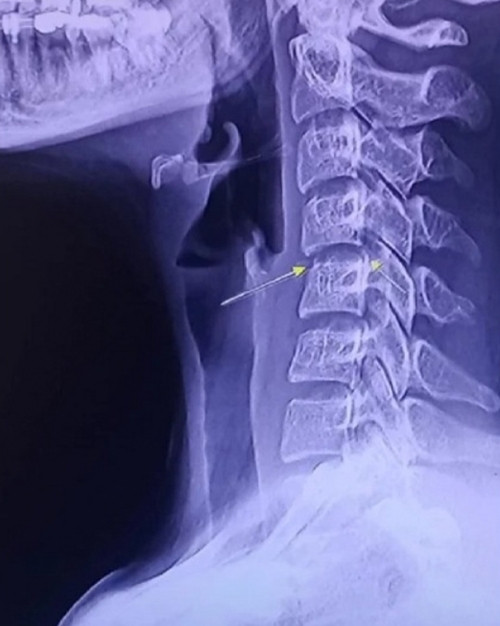

Các trang tin ở Thái Lan cảnh báo, cổ được coi là “điểm yếu” của cơ thể. Việc massage mạnh ở vùng này có thể làm tổn thương tủy sống hoặc các mạch máu đưa máu lên não.

“Người dân nên tránh đi massage vùng cổ hoặc cột sống. Những người bị đau đầu, nôn, hoa mắt, tê/ yếu chân tay cần gặp bác sĩ ngay lập tức” - một số trang tin ở Thái Lan cảnh báo.

Các trang tin cũng nói, động tác “vặn cổ” vốn không có trong massage truyền thống Thái Lan, nên thúc giục các nhân viên massage không thực hiện việc này để tránh làm khách hàng bị thương.

Bác sĩ thần kinh Thiravat Hemachudha người Thái Lan viết, việc vặn cổ hoặc massage cột sống ở vùng cổ có thể gây liệt. 177 bác sĩ thần kinh ở Mỹ báo cáo đã có những bệnh nhân bị liệt do nhồi máu não sau khi được nắn chỉnh cột sống cổ, trong đó có những bệnh nhân chỉ hơn 20 tuổi.

Một bệnh nhân bị liệt nửa người phải và phải nhập viện một tháng do cứ vặn cổ 3 lần/ngày. Bác sĩ Thiravat nhấn mạnh, người dân không nên thực hiện động tác vặn cổ vì có thể ảnh hưởng đến thị lực và sự cân bằng của cơ thể.